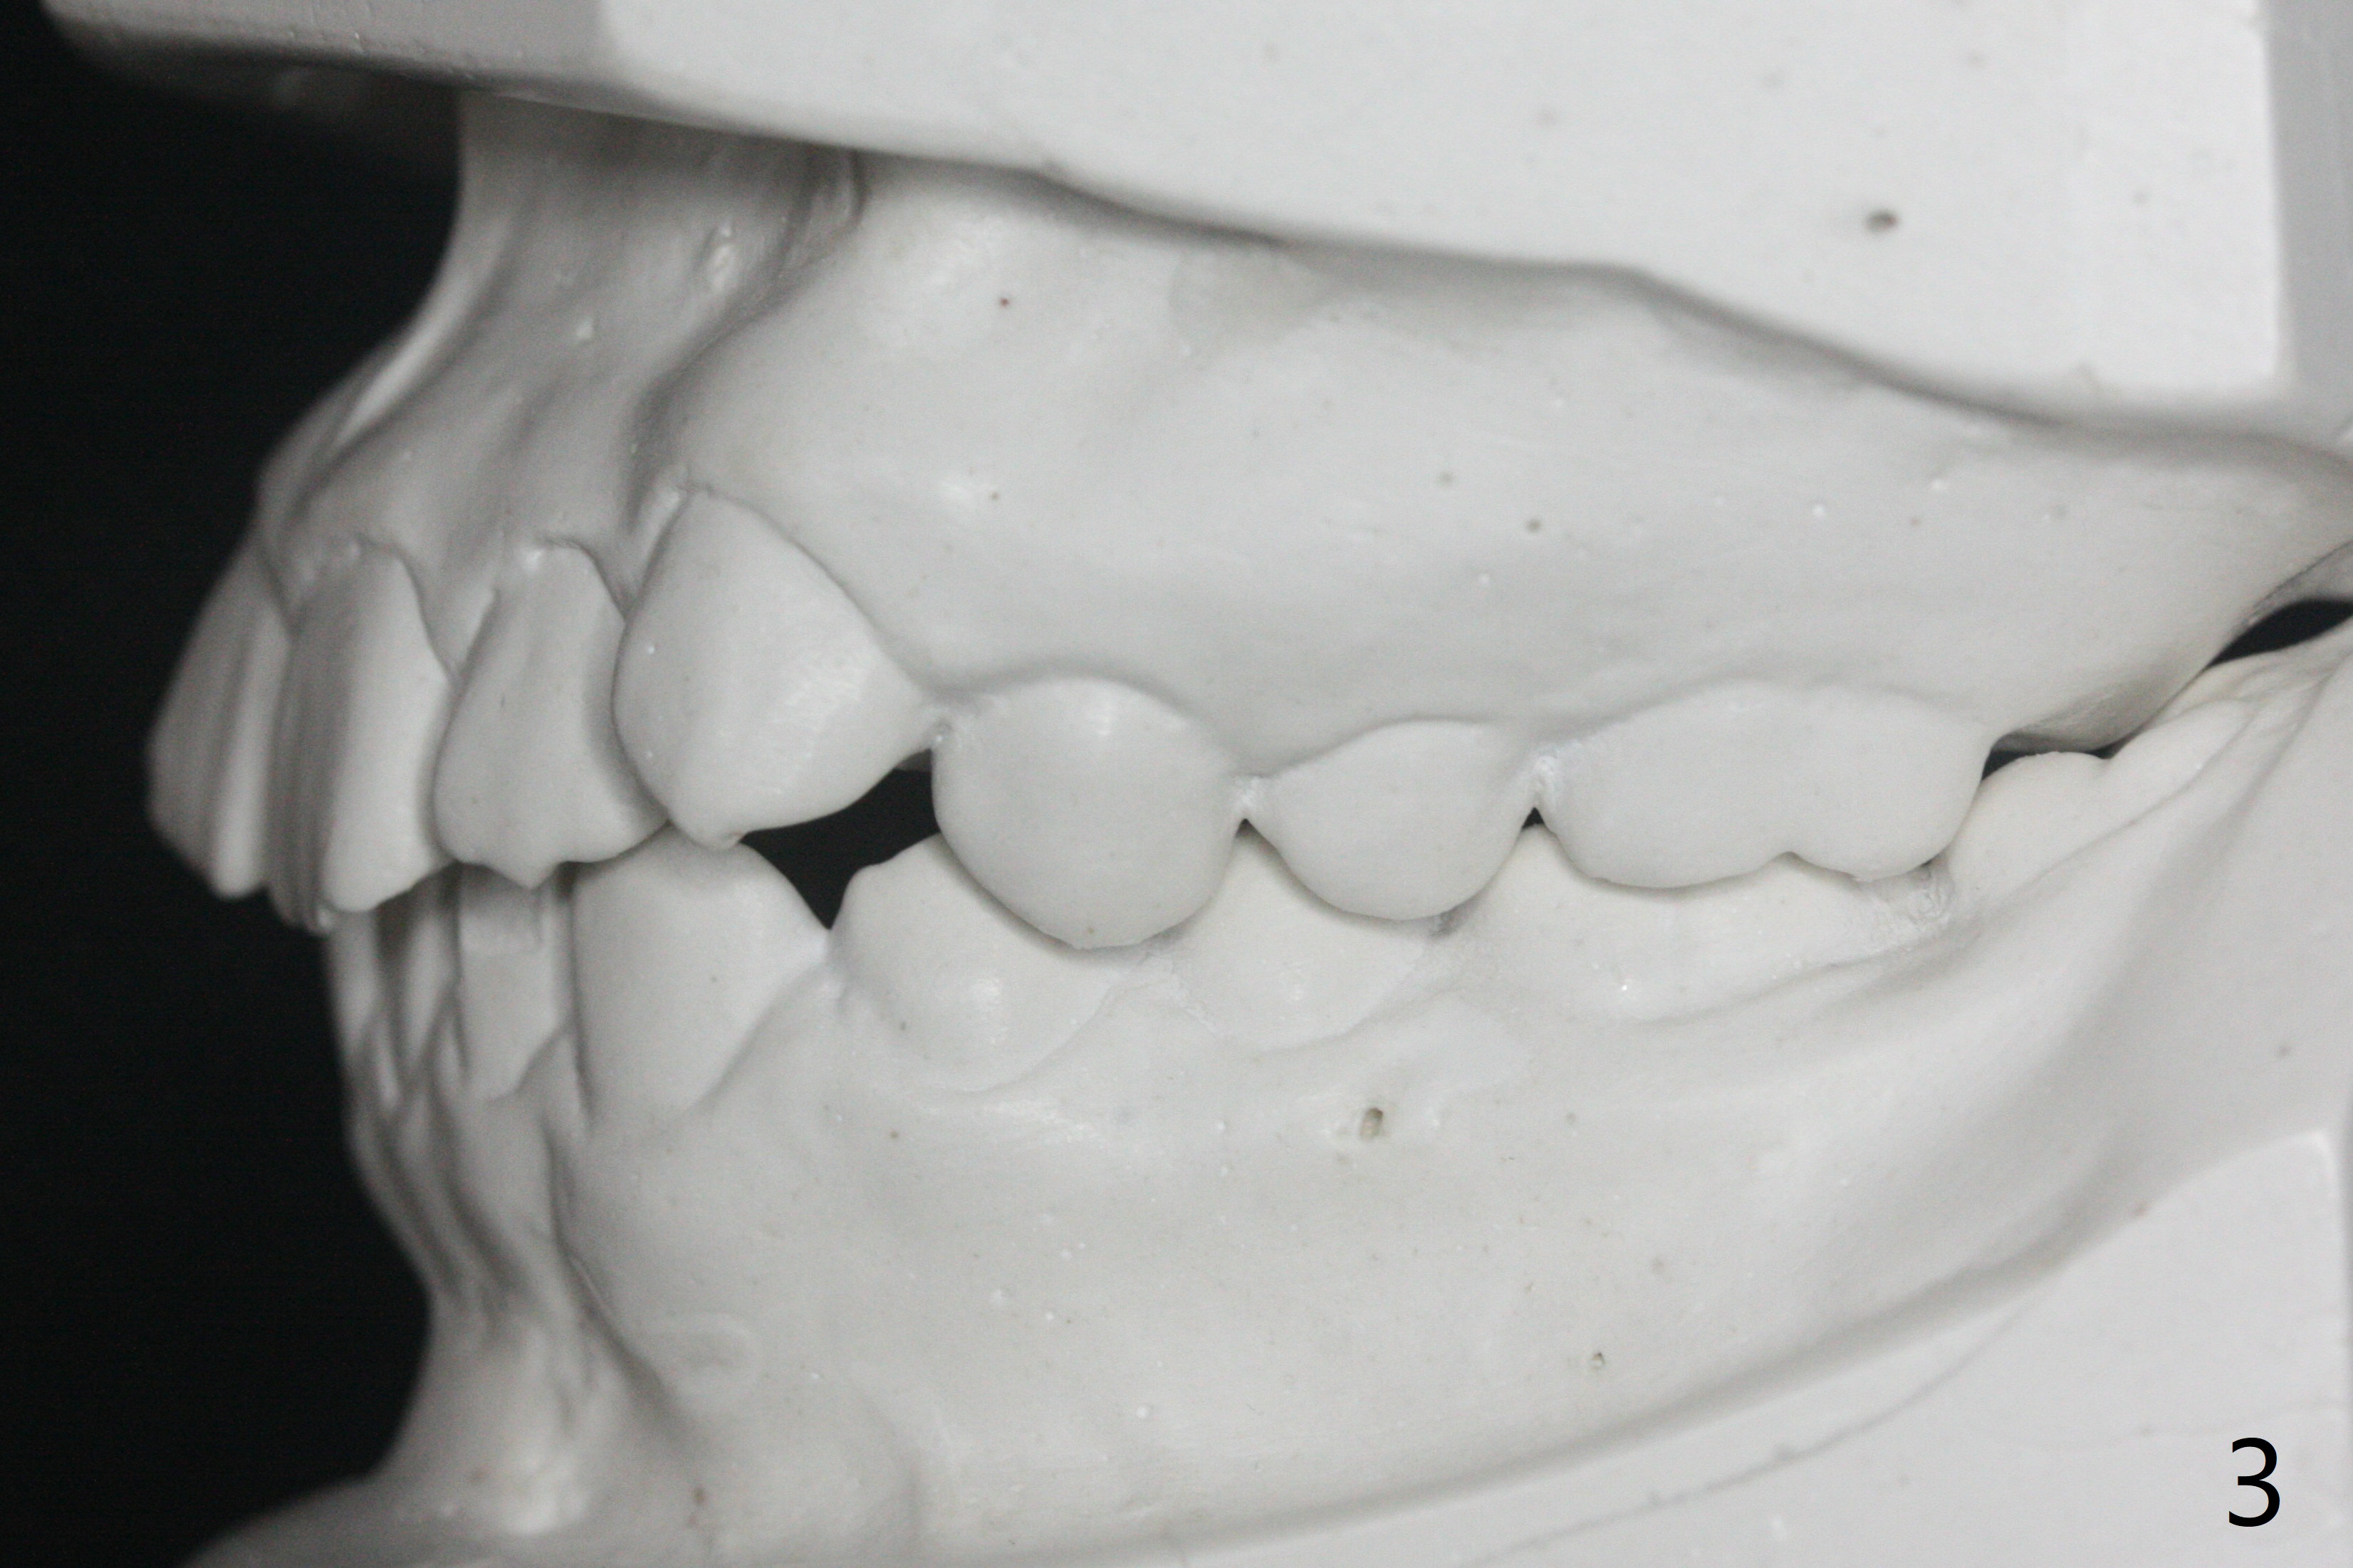

A 12-year-old woman has severe crowding including UL7 impaction (Fig.1-5), finishes non-extraction orthodontics at the age of 15 (Fig.1'-5') and returns for retainer remake at 19 (Fig.1''-5''). Four years post debanding, UL7 (Fig.4') seems to improve its position (Fig.4'').